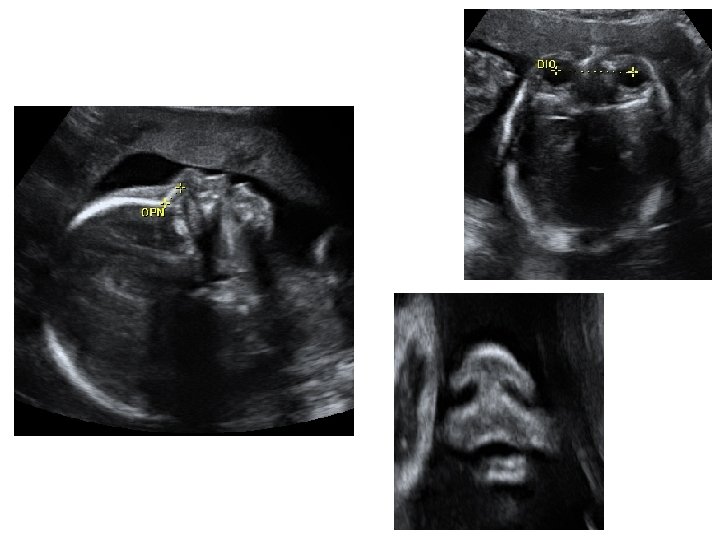

Échographie du 2ème trimestre • Entre 21 et 23 SA • Évaluer la croissance fœtale - pôle céphalique BIP : diamètre bipariétal PC : périmètre céphalique - abdomen fœtal CA : circonférence abdominale - extrémités : LF : longueur fémorale

• Étude morphologique approfondie - pôle céphalique : contours de la boite crânienne, volume des ventricules latéraux, structures de la ligne médiane, cervelet (aspect et mesure de sa largeur) - distance inter-orbitaire - coupe nez-lèvre - profil : menton aligné avec le front, mesure des OPN